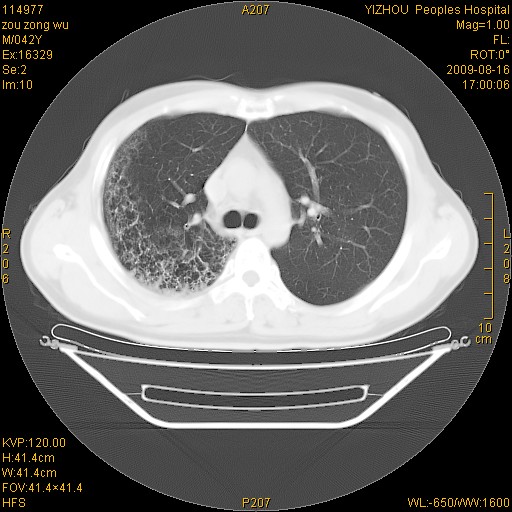

以下是引用zjzjr在2009-8-17 10:42:00的发言:[br]右侧间质性肺炎伴纤维化,右肺下叶肺囊肿伴感染(不除外外伤后引起),右肺野及胸壁软组织\\肝内见多发斑点状,中枪了吧.右侧胸膜肥厚\\粘连.